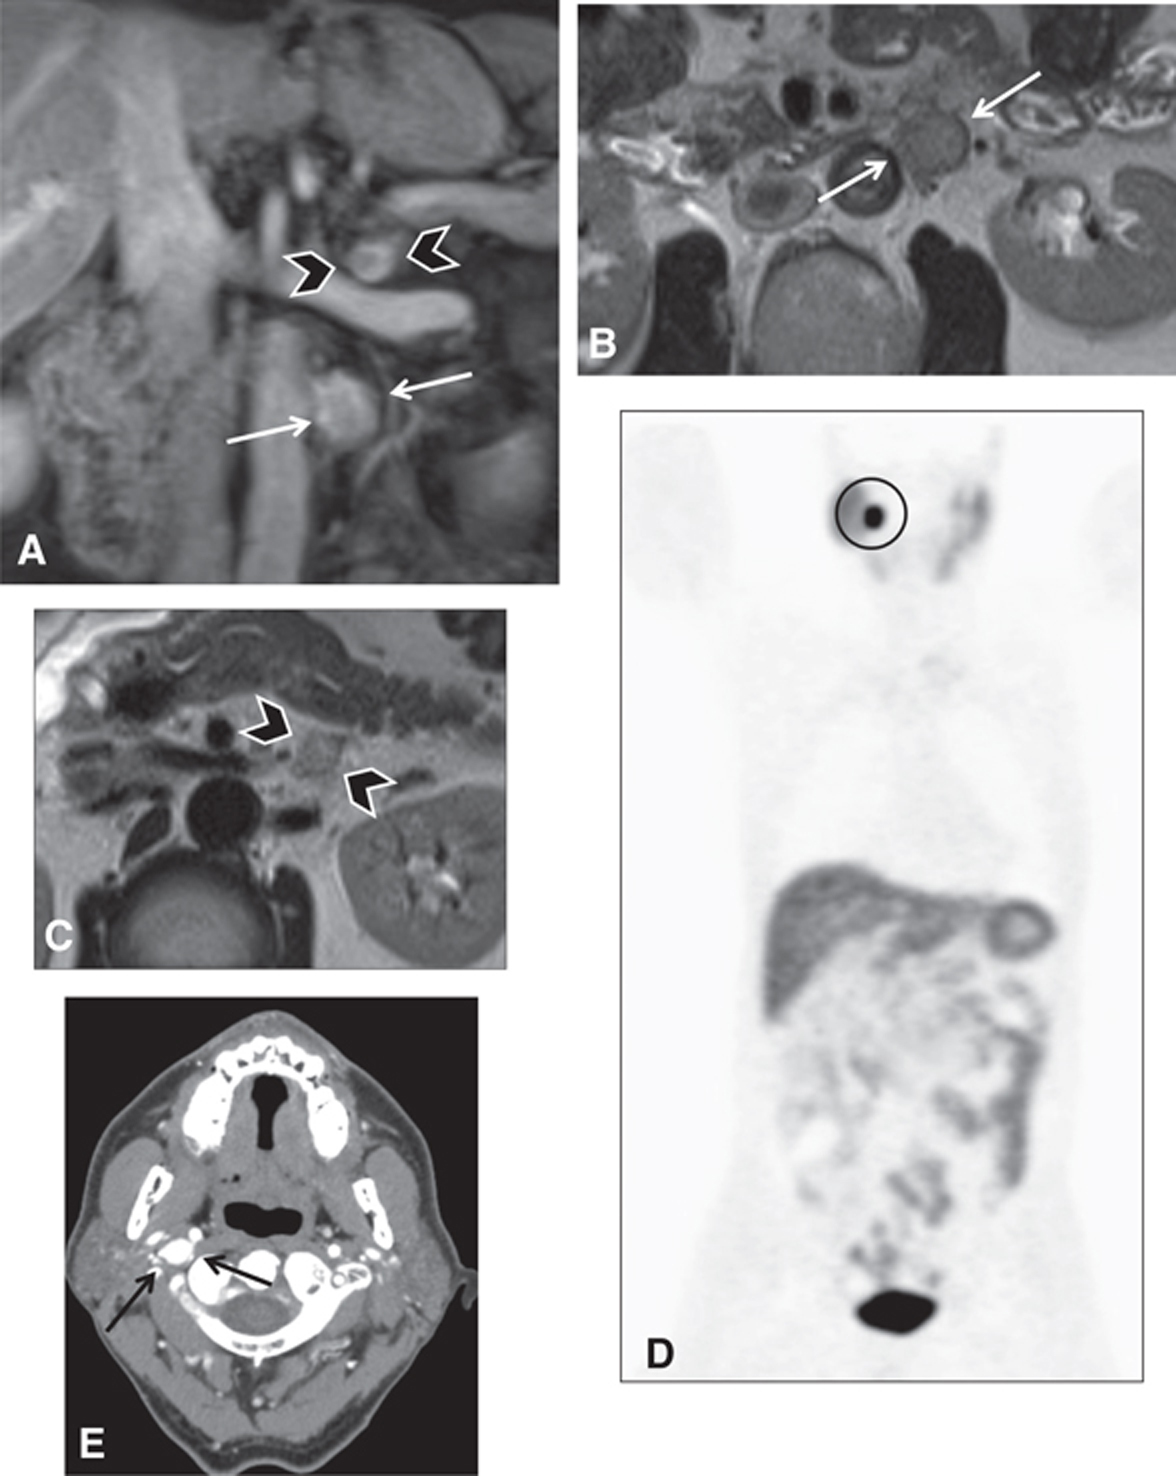

PPGLs can arise in various parts of the body, but they are classified by anatomic location into intra-adrenal and extra-adrenal sites. In contrast to head and neck paragangliomas, abdominal or trunk PPGLs arise from thoracic and abdominal sympathetic ganglia, producing catecholamines (8, 9). Imaging can be utilized at different stages of PPGL disease course. Diagnostic imaging for screening purposes can be offered for patients with germline mutations and high-risk syndromes (Figure 1), such as multiple endocrine neoplasia (MEN) types 2 and 3, von Hippel-Lindau (VHL), neurofibromatosis type 1 (NF1), and succinate dehydrogenase (SDH) mutations (10). This can be done with whole body positron emission tomography (PET) combined with computed tomography (CT) or magnetic resonance imaging (MRI) as in PET/CT or PET/MRI, or with anatomic imaging alone such as MRI or CT of the abdomen and pelvis. The frequency of imaging usually depends on the patient’s age and the specific underlying mutation or syndrome.

Fig 1

Figure 1 Several neuroendocrine tumors in a 60-year-old male patient with succinate dehydrogenase (SDH) subunit D mutation. (A, B, C) MRI of the abdomen demonstrates two left retroperitoneal lesions, one that is arising from the left adrenal gland (arrowheads) and a larger one more inferiorly, posterior to the fourth segment of the duodenum (white arrows) seen on (A) coronal fat-saturated post-contrast T1-weighted images and (B–C) fast spin echo T2 weighted images. The lesions were surgically resected. The left adrenal lesion was consistent with pheochromocytoma and the more inferior lesions were consistent with paraganglioma. (D) The patient underwent a gallium-68-DOTATATE scan to screen for additional neuroendocrine tumors. This demonstrated intense focal tracer uptake in the right neck (circle). (E) CT angiography and MRI of the neck (not shown) were performed for further characterization and the lesion (black arrow) was consistent with a glomus vagale paraganglioma.